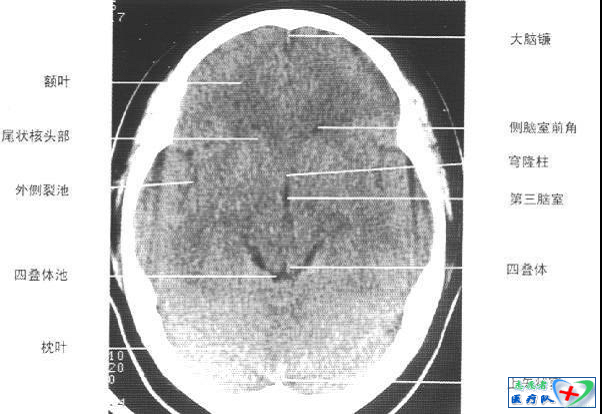

照片描述:第三脑室下部层面